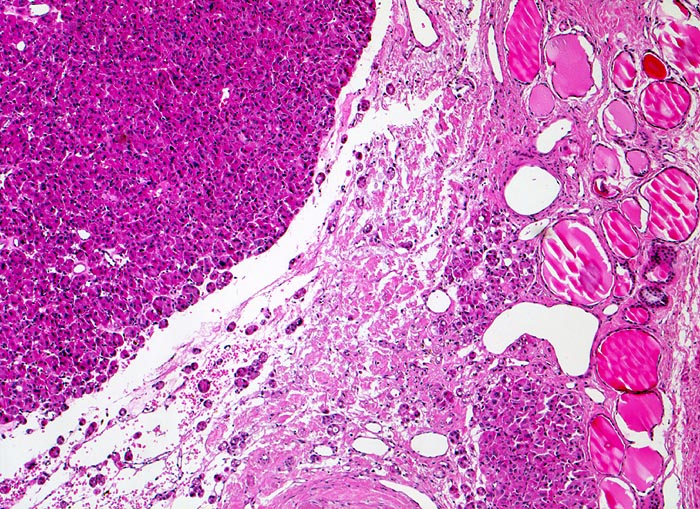

Die Subtypisierung der follikulären Karzinome erfolgt gemäss den Richtlinien der WHO 2017 nach dem Ausmass der Invasivität in minimal invasive (nur Kapseldurchbrüche), gekapselt angioinvasive und grob invasive Karzinome mit meist schon makroskopisch sichtbaren zahlreichen Kapseldurchbrüchen und Gefässeinbrüchen. Follikuläre Schilddrüsenkarzinome mit zahlreichen Gefässeinbrüchen und grob invasive Tumoren haben eine schlechtere Prognose.

Entscheidend für die Diagnose eines follikulären Schilddrüsenkarzinoms in Abgrenzung zu einem gutartigen follikulären Schilddrüsenadenom ist der Nachweis eines Durchbruchs der Tumorkapsel (> 2753) (> 4951) und/oder ein Einbruch in Venen (> 4953) (> 8265) innerhalb oder jenseits der Tumorkapsel sowie das Fehlen morphologischer Kernmerkmale eines papillären Schilddrüsenkarzinoms. Zytologische Atypien kommen auch bei gutartigen follikulären Adenomen vor und sind deshalb kein Malignitätsmerkmal. Da Kapseldurchbrüche und Gefässeinbrüche nur am Gewebsschnitt diagnostiziert werden können, ist eine präoperative zytologische Diagnose eines follikulären Schilddrüsenkarzinoms anhand der Feinnadelpunktionszytologie nicht möglich.

• Kapseldurchbrüche: Die breite bindegewebige Kapsel wird an mehreren Stellen pilzförmig vorgewölbt und an einigen Orten vollständig durchbrochen.

• Keine eindeutigen Gefässeinbrüche (keine Tumorthromben oder endothelialisierte Tumorzapfen in Venen der Kapsel oder jenseits der Kapsel). Das sollte der Kliniker dem Pathologen mitteilen: